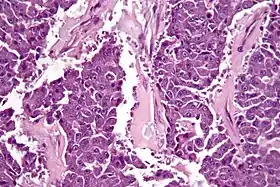

![]() صورة مجهرية لسرطانة الخلايا العنيبية للبنكرياس بصبغة الهيماتوكسيلين واليوزين. صورة مجهرية لسرطانة الخلايا العنيبية للبنكرياس بصبغة الهيماتوكسيلين واليوزين. | |

من ناحية علم الشكل النسيجي فإنه يُشبه ورم الخلايا العنيبية للبنكرياس وعادة ما يكون لديه كمية معتدلة من السيتوبلازم الحبيبي الذي يصبغ مع كل من ملون حمض شيف الدوري ودياستاز ملون حمض شيف الدوري.[4]

عادةً ما يظهر الفحص المجهري الضوئي لخزعة سرطان الخلايا العنيبية مظهرًا حبيبيًا، وعادة ما تكون الكيمياء النسيجية المناعية إيجابية بالنسبة للتربسين والكيموتريبسين والليباز. في الاختبارات الجينية يُعثر على الجينات/البروتينات المعدلة لـ بي53 وSMAD4 وبروتين داء السلائل القولوني الورمي الغدي وARID1A وGNAS.[5]